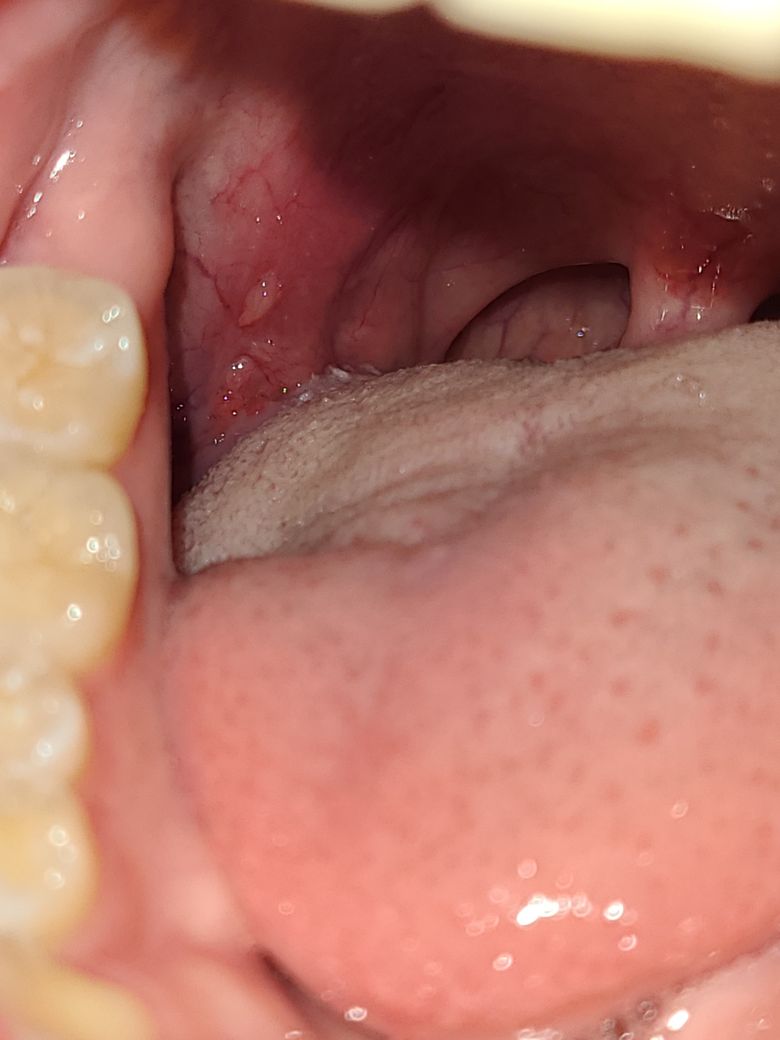

입안에 종양 같은게 있는데 뭘까요??

얼마전에 혀클리너를 너무 강하게 사용해서 상처가 난 거 같기도 한데 큰 병은 아닌지 걱정되네요

사진에 보이는 것은 혀의 옆면에 위치한 부분으로, 혀 클리너 사용으로 인해 발생한 자극으로 보일 수 있습니다. 이런 종류의 자극이나 손상은 때때로 부기, 발적 또는 작은 궤양의 형태로 나타날 수 있으며, 대부분은 시간이 지나면 자연스럽게 치유됩니다.

그러나, 이 부위가 지속적으로 아프거나 크기가 커지거나 다른 증상이 동반되는 경우는 이비인후과 나 구강안면외과의 진료를 받으시기 바랍니다.